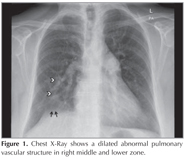

Chest X-ray showed a dilated abnormal pulmonary vascular structure (arrowheads) in right middle and lower zone (Figure 1). There was also seen irregularity of the medial right hemidiaphragm (short arrows). Axial image of contrast enhanced thorax multi detector computed tomography (MDCT) showed dilated right superior pulmonary vein (RSPV) (Figure 2, asterisk). The middle pulmonary vein also drained into RSPV (short arrows). Coronal reformatted MDCT images revealed mild right lung hypoplasia, elevation of right hemidiaphragm (short arrow) and draining the RSPV (asterisk) to the vena cava inferior (VCI) (arrowhead) (Figure 3). Volume rendering MDCT image showed relationship between RSPV (asterisk) with VCI (arrowhead) (Figure 4). There was also seen right pulmonary artery (dagger) and portal vein (short arrow). Final diagnosis of the patient was partial anomalous right pulmonary venous connection (Scimitar syndrome).

Figure 1